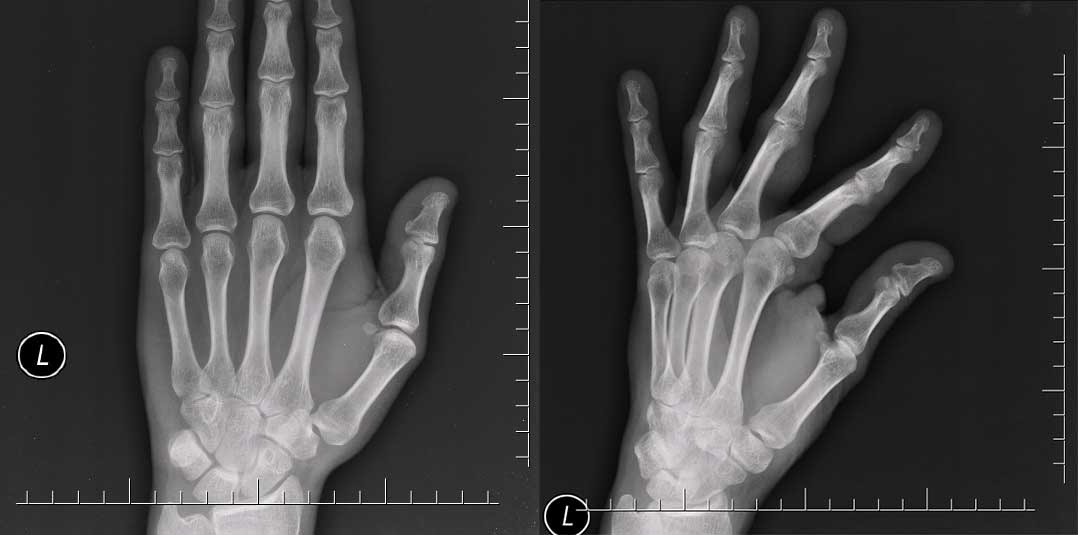

在这两个示例中,通常需要多个视图来评估正在发生的事情。例如,手部的 X 光片可能仅在手部处于特定姿势或角度时才显示骨折。

尽管如此,捕捉手的正面视图是标准的。

手的正面视图。

第 3 和第 4 中节指骨基底部的小骨折大多仅在右图可见。